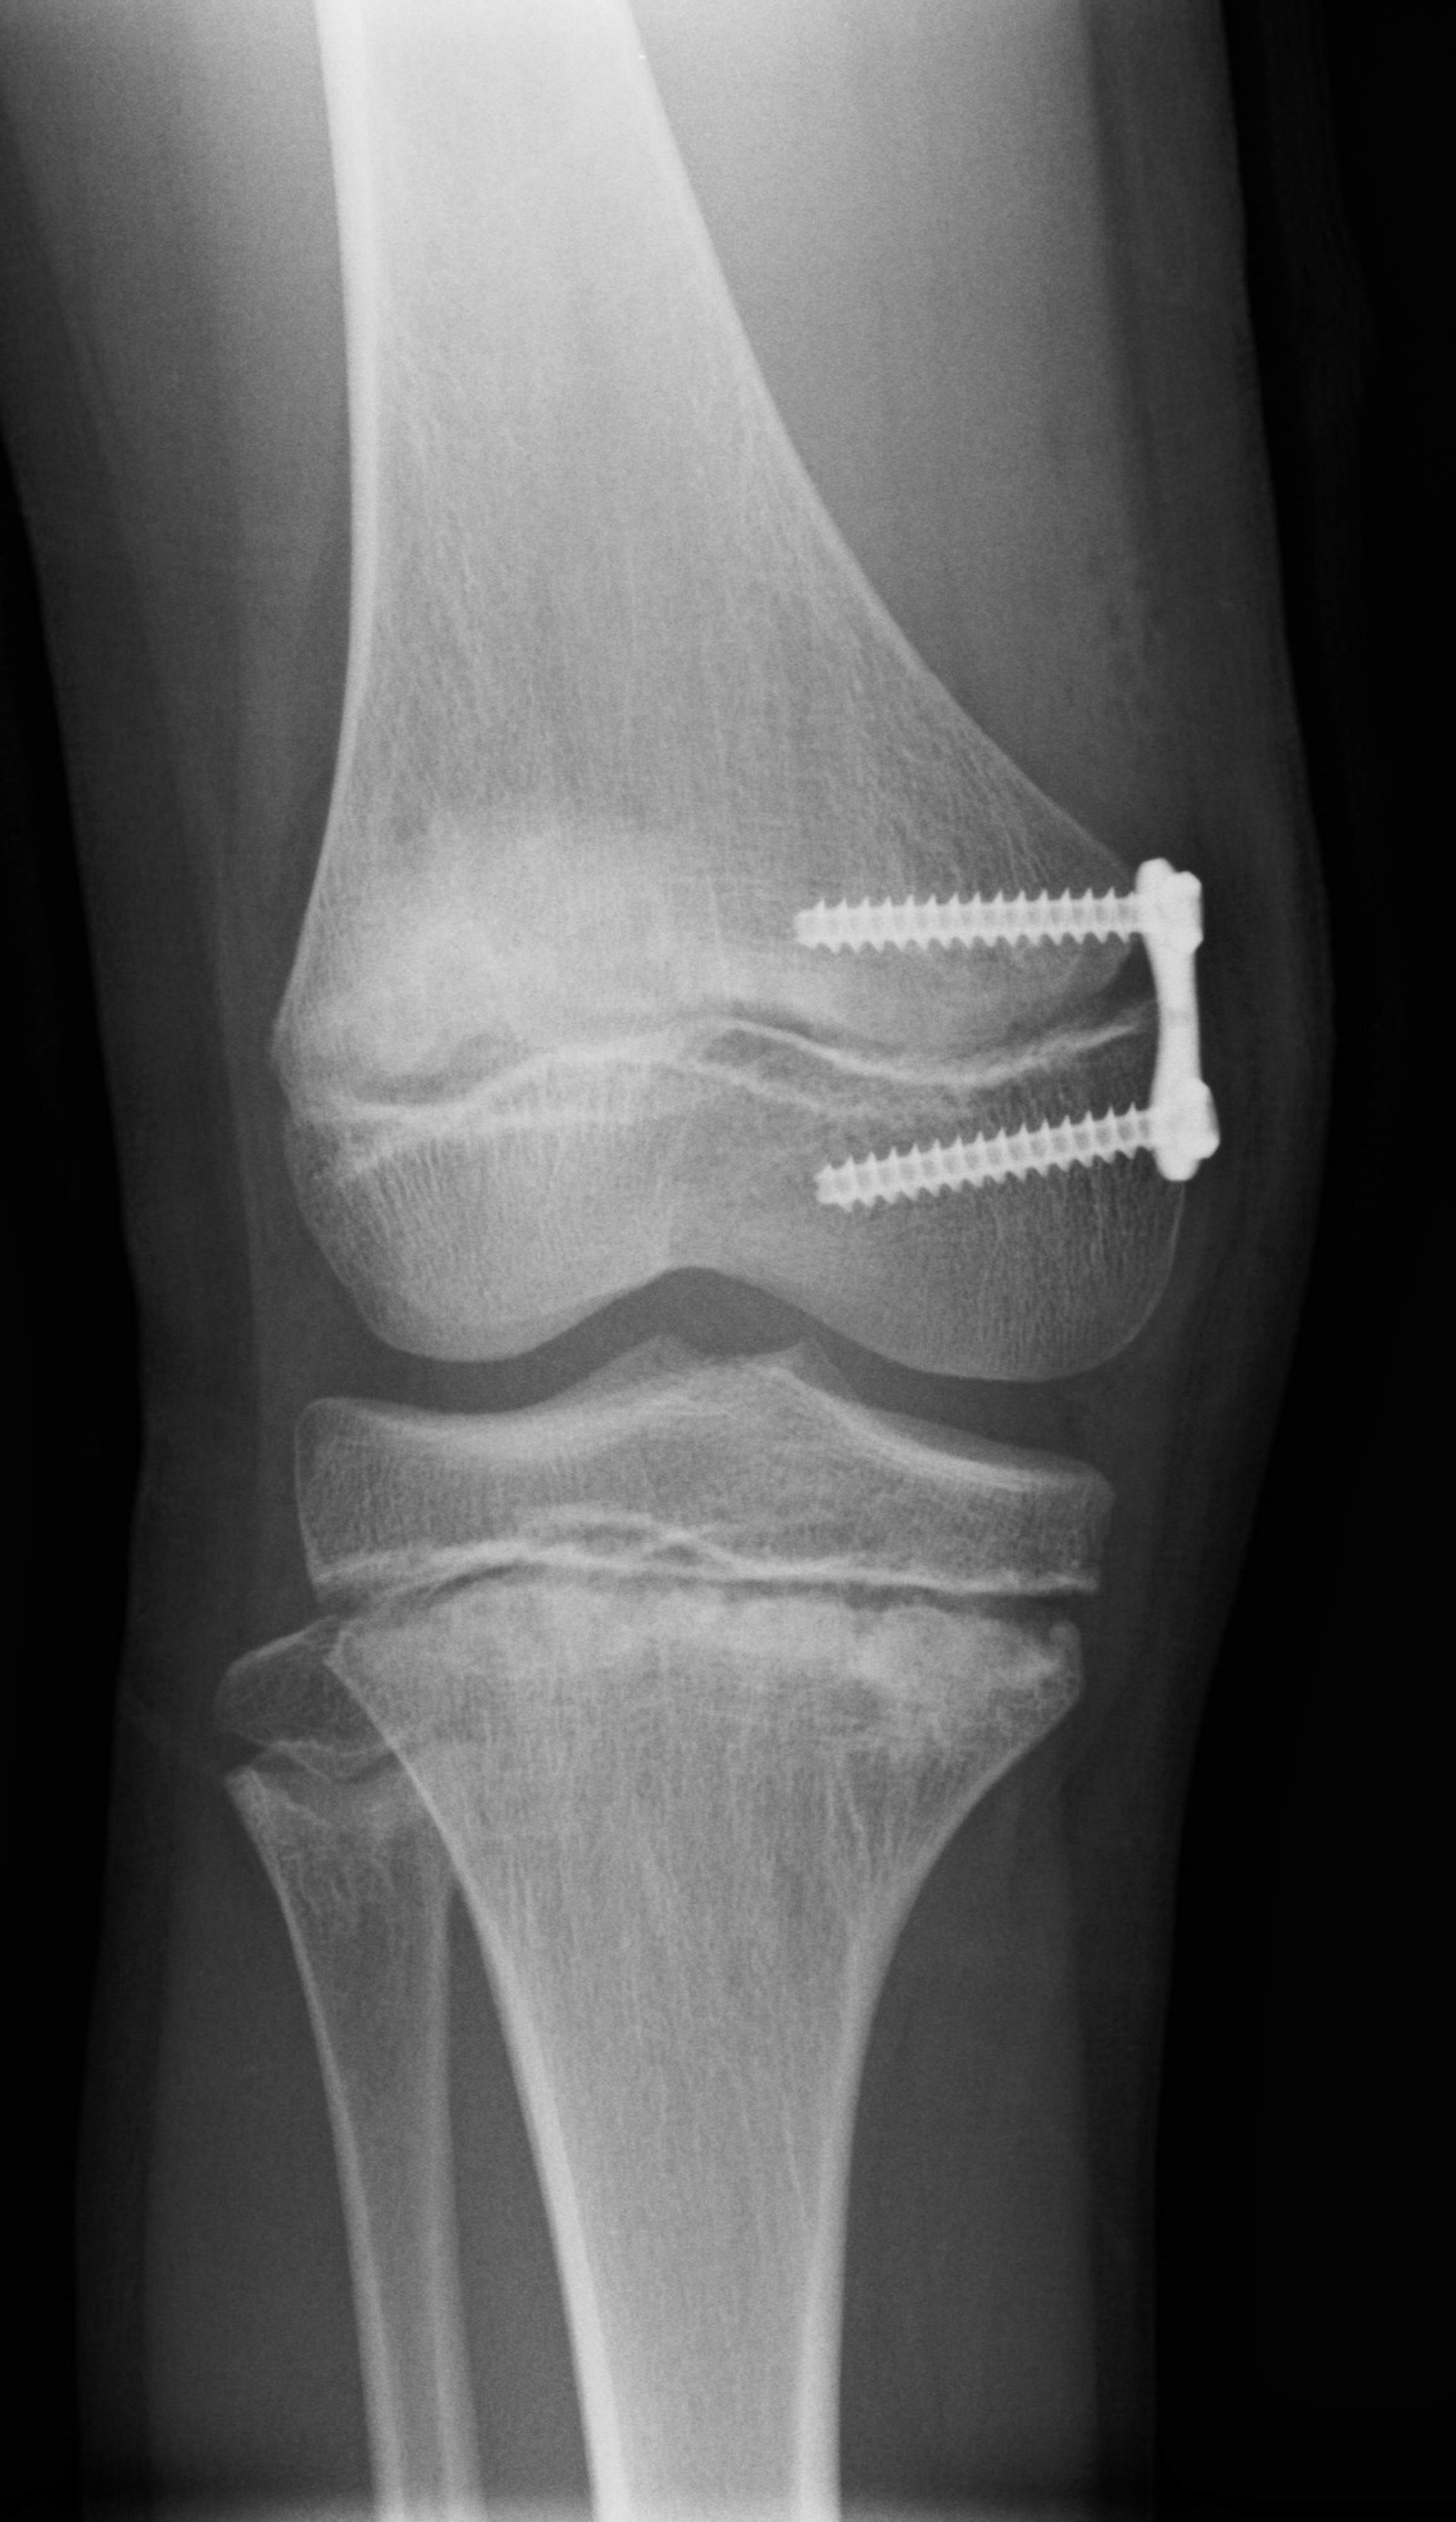

Länkisääret ja pihtipolvet todetaan katsomalla lasta liikkuessa ja paikallaan seisten. Tarpeen mukaan alaraajojen kuvantaminen röntgentutkimuksella antaa lisätietoa alaraajojen asennosta ja tukee hoitovalintaa.

Lääkäri arvioi seurannan tai hoidon tarpeen. Leikkaushoito tulee harvoin kyseeseen. Yleisimmässä leikkausmenetelmässä alaraajojen asentoon pyritään vaikuttamaan hyödyntämällä jäljellä olevaa kasvua. Nukutuksessa tehtävässä toimenpiteessä asetetaan kasvulinjan kohdalle levy, joka estää kasvua levyn puoleiselta reunalta korjaten virheasentoa. Levy yleensä poistetaan, kun korjaus on saavutettu.